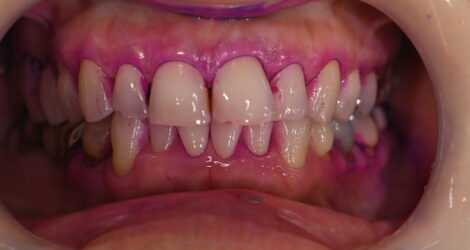

└4MTA

今回はMTAセメントの症例をご紹介します?

☆クリーニングで虫歯が見つかり処置

☆左上4

?MTAセメント?

・マイクロ下で処置、動画も撮影

・処置時間1時間

・¥55,000

【担当医】北野 展久